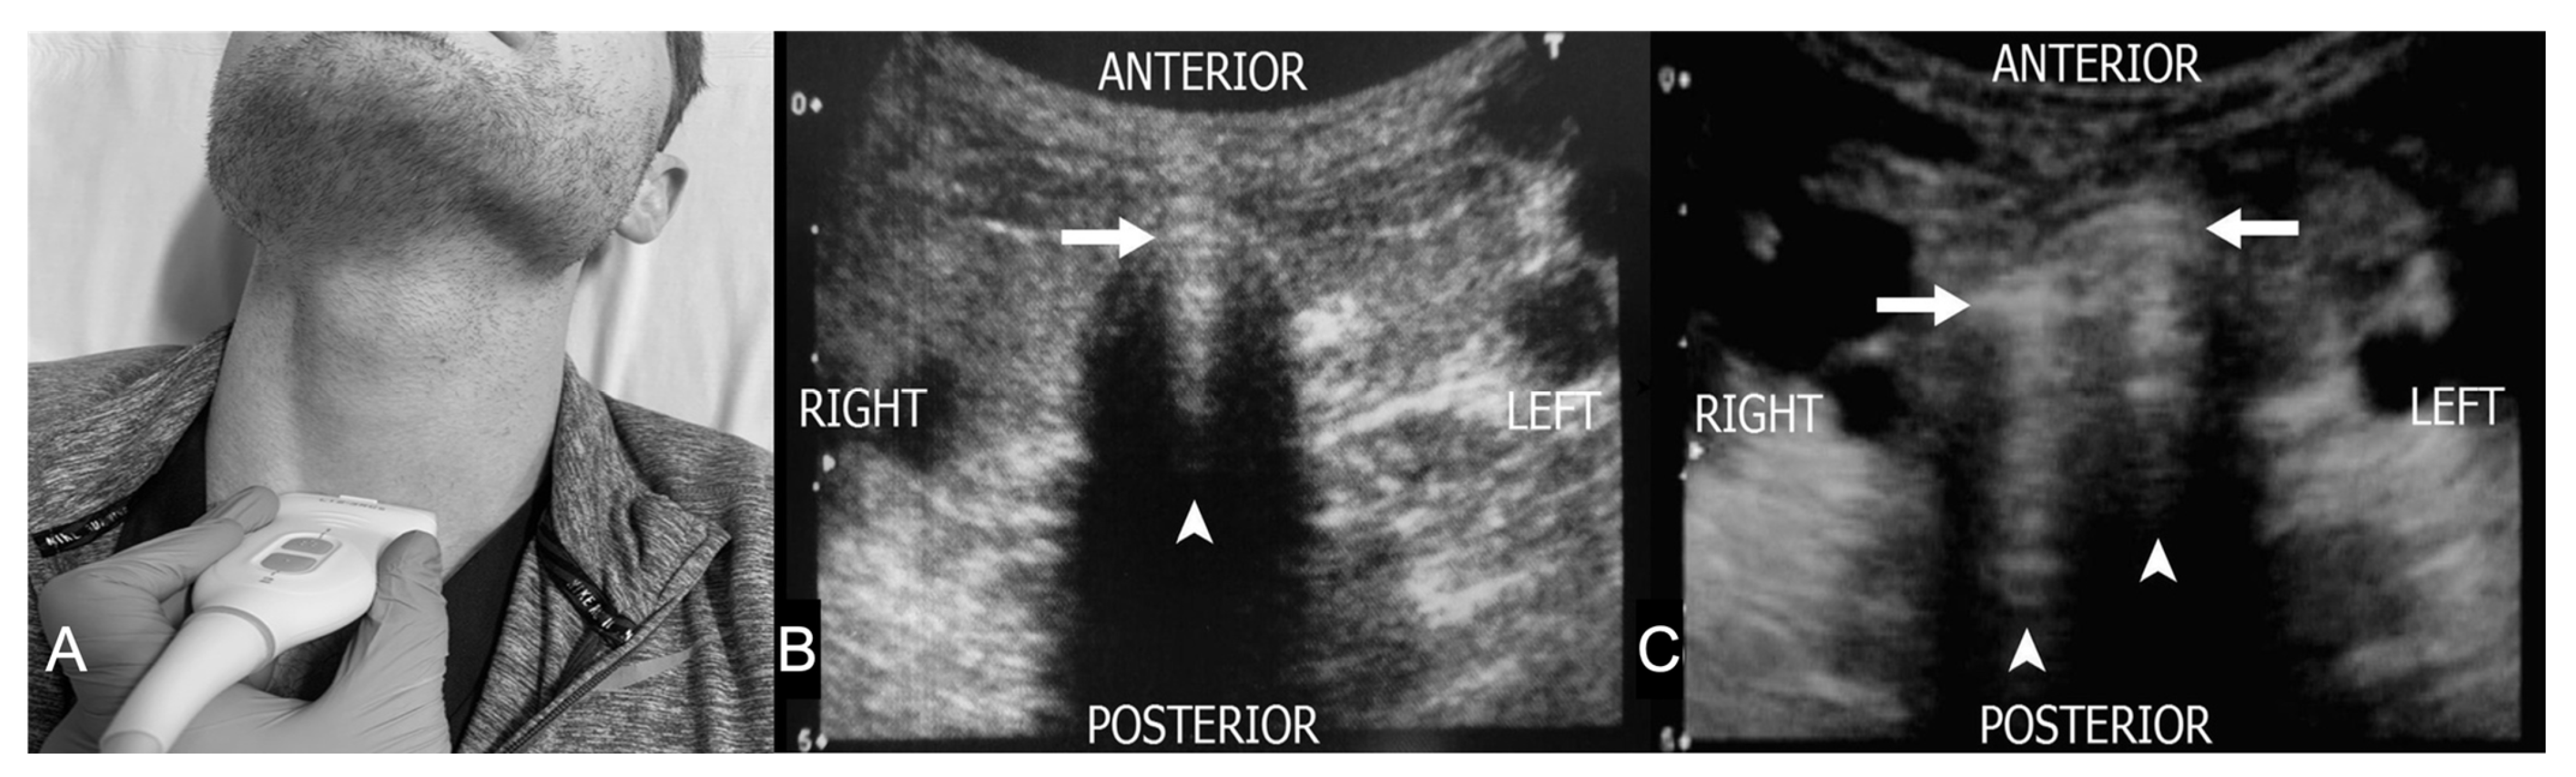

3. Probe Selection and Technique

4.5. Suprasternal View